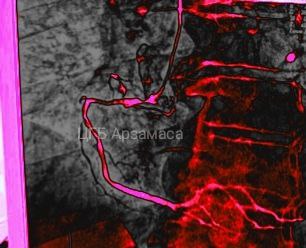

В Центральной городской больнице Арзамаса впервые применили внутрисосудистое ультразвуковое исследование (УЗИ) при лечении пациента с инфарктом. Об этом сообщил телеграм-канал "Бокал прессека".

С помощью внутрисосудистого УЗИ врачи могут точно определить диаметр артерии и протяженность атеросклеротической бляшки. Это помогает установить стент с максимальной точностью и избежать ошибок, которые возможны при компьютерной диагностике. По словам специалистов, такие погрешности могут достигать 30%.

Как пояснил заведующий отделением рентгенохирургических методов диагностики и лечения ЦГБ Арзамаса Илья Шумаков, новая методика позволяет контролировать, насколько плотно стент прилегает к стенкам сосуда. Также она помогает выявить его неправильное расположение и устранить дефекты с помощью баллонной ангиопластики.

"Это особенно важно при сложных случаях имплантации, где одной ангиографии недостаточно", — отметил врач.